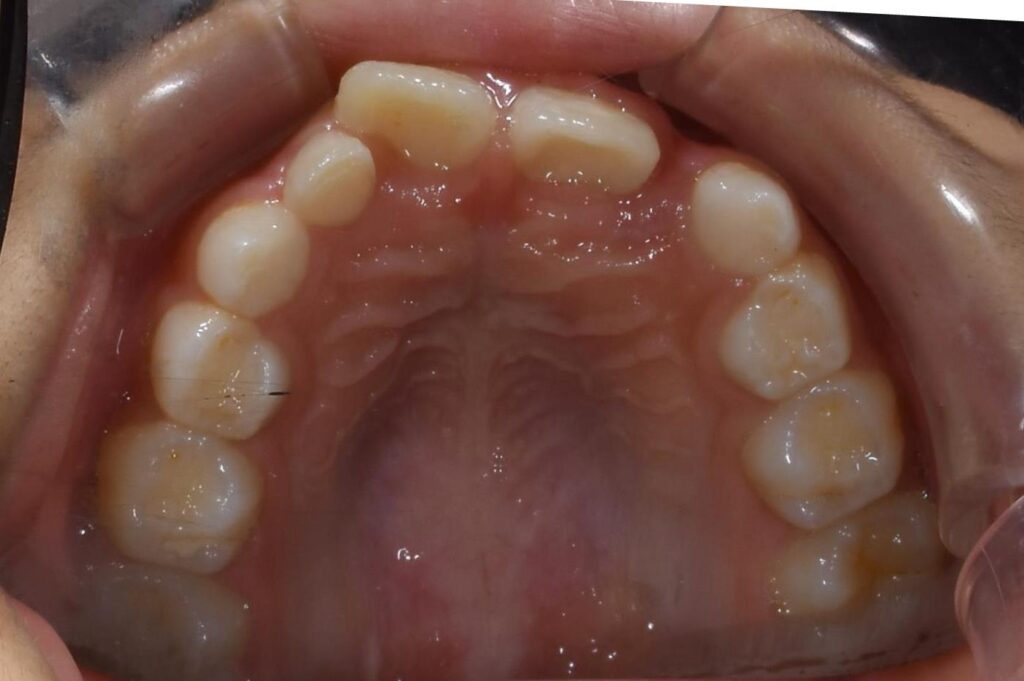

まずは、初診時の上顎の写真です。

【矯正治療前】

画面向かって右の前歯が内側に生えており、反対側の前歯とかなり位置がずれています。

そのため、年齢的に抜けてるべき乳歯が残存しています。